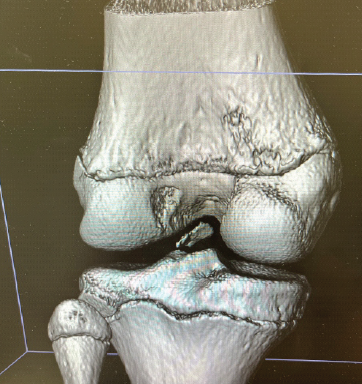

Simultaneous Anterior Cruciate Ligament Avulsion Fracture with Bilateral Posterior Meniscal Root Tears of the Knee: A Case Report

Deem Alsedais , Bader Majed Aljadaan , Hamad H Aldakhil Allah , Abdullah Adel Al-Nasser , Ibrahim Ababtain ………………………………p.222-226

Single-Stage Management of Anterior Cruciate Ligament Tear with Dual Menisci Bony Root Avulsion: A Rare Case Report and Review of Literature

Mukesh Garg , Vishesh Verma